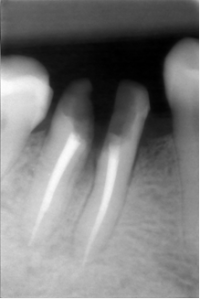

Nettoyage inter-radiculaire.

Reprise du traitement endodontique , séparation des racines et curetage inter-radiculaire.